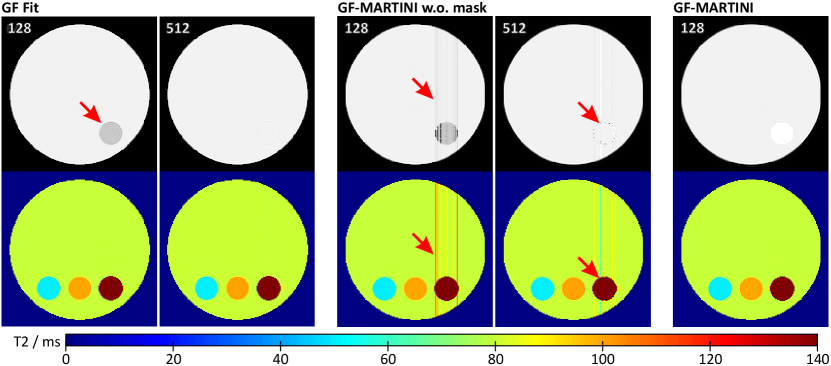

Figure 3

shows spin-density and T2 maps of a noiseless numerical phantom reconstructed by pixel-wise GF fitting and the proposed GF-MARTINI method without and with the adaptive validity mask. The time-domain data points (echoes) per pixel were derived from either or samples in the frequency-domain that define the degree of oversampling on the z-plane. As expected, even for the pixel-based reconstruction (Fig. 3, left), both the spin-density and T2 map yield errors for the compartment with the longest T2 of when using only samples (, arrow). However, T2 values of the remaining compartments were accurately reconstructed with less than deviation from the true value. The problem may largely be reduced by extensive oversampling with frequency-domain samples () as revealed by a mean T2 value of in the rightmost compartment, which is less than deviation from the true value.

Figure 3 (center) shows the corresponding maps for GF-MARTINI when using iterations per column and an optimized but constant gradient scaling for every pixel (no masking of invalid regions). The results in () not only demonstrate the expected deviations for the long-T2 compartment, but also artifacts (arrows) in the remote part of the columns that comprise the compartment. While the effect is again reduced for the higher number of frequency-domain samples (), residual artifacts originating from model violations at the compartment borders persist.

Finally, Fig. 3 (right) demonstrates that all artifacts can be avoided by the proposed adaptive mask, even for moderate oversampling of samples. In this case the numerical results are in good agreement with the corresponding pixel-based GF fit () except for the masked-out right compartment. Here, the values for GF-MARTINI are mainly influenced by the applied L2 regularization, which is not included in the pixel-based fit.